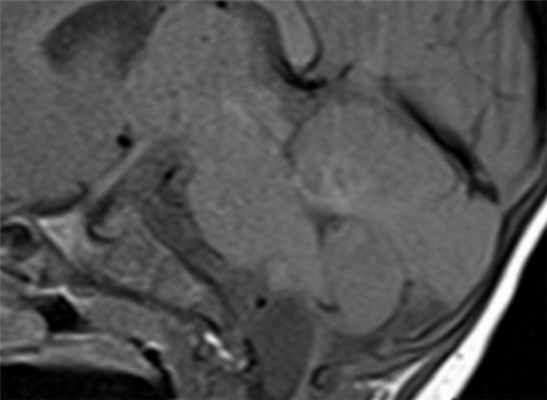

о Корональные Т2-ВИ: оценка взаимоотношения с хориоидальной щелью(а) МРТ, Т1 -ВИ, сагиттальный срез: определяется крупная киста хориоидальной щели, оказывающая масс-эффект на прилегающий гиппокамп.

Наиболее часто такие кисты являются случайно находкой, однако в данном случае сообщается о предположительной связи кисты с комплексными парциальными судорожными приступами.

(б) MPT, FLAIR, аксиальный срез: у этого же пациента тотчас позади крючка гиппокампа определяется изоинтенсивная киста хориоидальной щели.

Киста смещает височный рог бокового желудочка и деформирует нормальный гиппокамп. Кисты хориоидальной щели имеют ликворную интенсивность сигнала на всех последовательностях. (а) МРТ, Т2-ВИ, корональный срез: определяется киста хориоидальной щели, смещающая височный рог бокового желудочка и вызывающая сдавливание и деформацию гиппокампа и парагиппокампальной извилины.